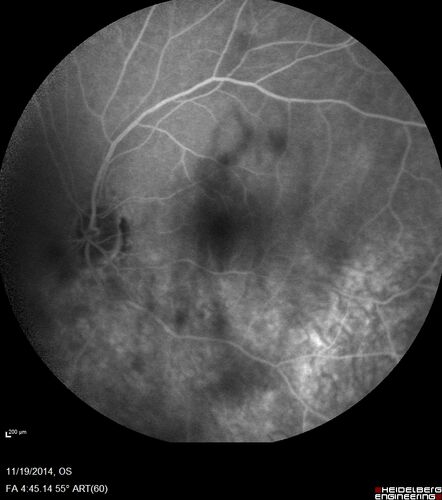

65 year old man with Sturge weber and a choroidal hemangioma in the left eye.  (See other images under sturge weber on this website). Has ongoing problem with his left eye.  Now with Blurred vision in the right eye gradually worse the last few weeks.  He has had a vitrectomy in the right eye 4 years ago for floaters.  Laser for tears and cryo in the right eye 5 years ago. He is on Dorzolamide and Lumigan for glaucoma.

VA 20/32 OD, 20/40 OS

IOP 23 OD, 19 OS